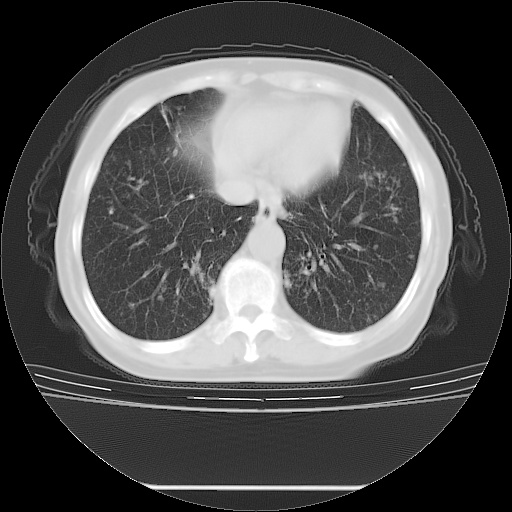

ct示两肺粟粒状病灶,以两肺上叶尖后段及下叶背段分布为主;首先考虑结核。请战友们分析。

考虑 1 弥漫性泛细支气管炎, 2 结核不除外/.  有小叶中心结节 和 树芽征!!

病灶以结节为主,大部分边界清楚,分布不均,病灶形态较单一,偶见空泡征,纵膈淋巴结肿大钙化,无结核中毒症状考虑 感染性病变【真菌类可能性大】,细支气管肺泡癌。其他待排

纵隔见肿大淋巴结并钙化,首先考虑结核,但感觉小结节像“挂果”征,分布位于支气管边缘,所以不排外肺泡癌,建议抗唠后复查吧?不然是癌的话,也不好治吧?化疗?